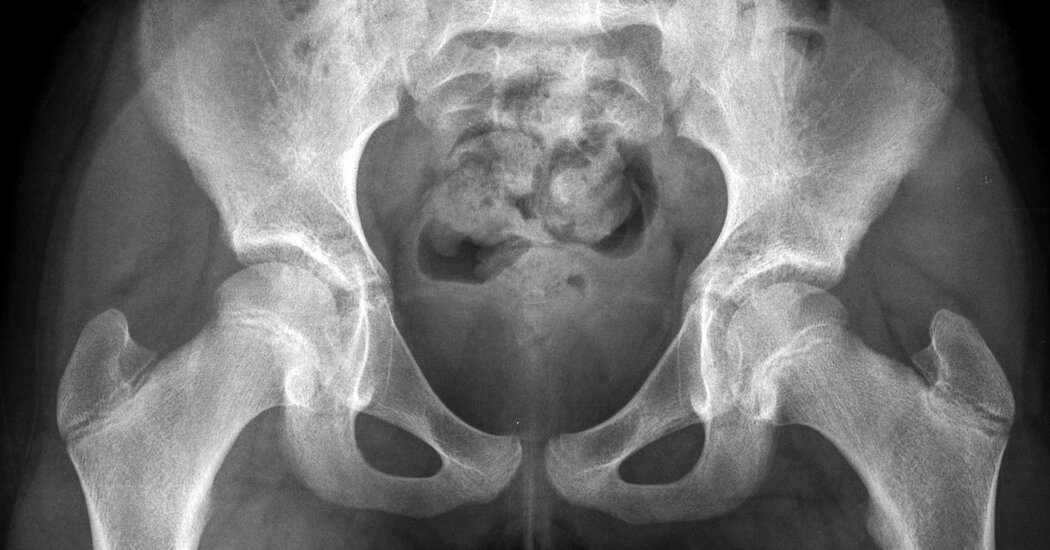

The critical issue is that the pelvis of a child is too small to allow passage of even a small fetus, said Dr. Ashok Dyalchand, who has worked with pregnant adolescent girls in low-income communities in India for more than 40 years.

“They have long labor, obstructed labor, the fetus bears down on the bladder and on the urethra,” sometimes causing pelvic inflammatory disease and the rupture of tissue between the vagina and the bladder and rectum, said Dr. Dyalchand, who heads an organization called the Institute of Health Management Pachod, a public health organization serving marginalized communities in central India.

“It is a pathetic state particularly for girls who are less than 15 years of age,” he added. “The complications, the morbidity and the mortality are much higher in girls under 15 than girls 16 to 19 although 16 to 19 has a mortality twice as high as women 20 and above.”

In the cases he has seen, early pregnancy arrests the very young mother’s physical growth, and also often her mental development because many girls leave school and lose normal social interaction with peers, he said. But while an anemic mother struggles to carry the pregnancy, fetuses appropriate nutrients and continue to grow, until they have well surpassed what a young mother’s pelvis can deliver.

“They go to labor for three days, four days, five days, and after that labor, usually the baby is dead. And then when the head is collapsed, then the baby is delivered,” said Dr. Syed, who is one of South Asia’s pre-eminent experts on the repair of obstetric fistula, a common outcome of obstructed labor in pregnant girls.